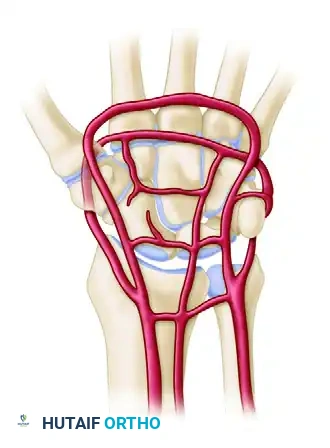

Vascular Anatomy and Circulation

The extraosseous blood supply to the carpus is derived from the terminal branches of the radial, ulnar, and anterior interosseous arteries. These form a highly redundant network of three dorsal and three palmar transverse arterial arches.

Dorsal Arterial Arches

- Dorsal Radiocarpal Arch: Located at the radiocarpal joint; supplies the proximal poles of the scaphoid, lunate, and triquetrum.

- Dorsal Intercarpal Arch: The largest dorsal arch, located between the proximal and distal rows. It supplies the distal carpal row and anastomoses with the radiocarpal arch.

- Basal Metacarpal Arch: Highly variable; supplies the distal carpal row and carpometacarpal joints.

Palmar Arterial Arches

- Palmar Radiocarpal Arch: Supplies the palmar surfaces of the lunate and triquetrum.

- Palmar Intercarpal Arch: Highly variable; rarely contributes significant nutrient vessels to the intraosseous carpus.

- Deep Palmar Arch: Consistent and robust; communicates directly with the dorsal basal metacarpal arch.

Clinical Pearl: The scaphoid and lunate rely heavily on retrograde intraosseous blood flow. The scaphoid receives 70-80% of its blood supply via dorsal ridge vessels entering distally, making proximal pole fractures highly susceptible to avascular necrosis (AVN) and nonunion.